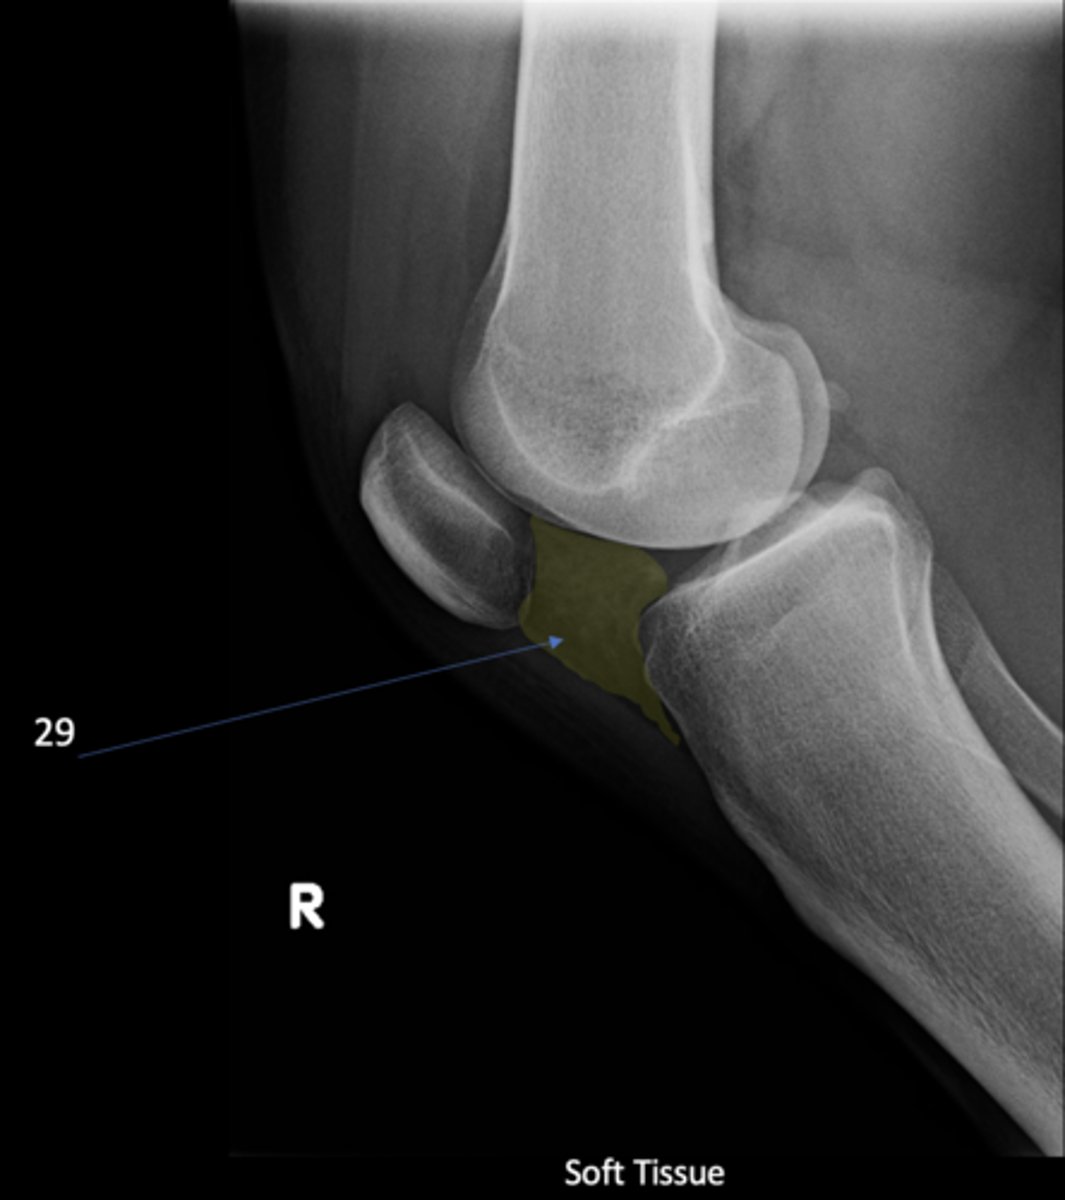

Infrapatellar pouch

ID 29

<p>ID 29</p>

92

New cards

Hoffa's fat pad

Another term for infrapatellar pouch

<p>Another term for infrapatellar pouch</p>

Quadriceps tendon

ID 30

<p>ID 30</p>

Prefemoral fat pad

ID 31

<p>ID 31</p>

Suprapatellar pouch

ID 32

<p>ID 32</p>